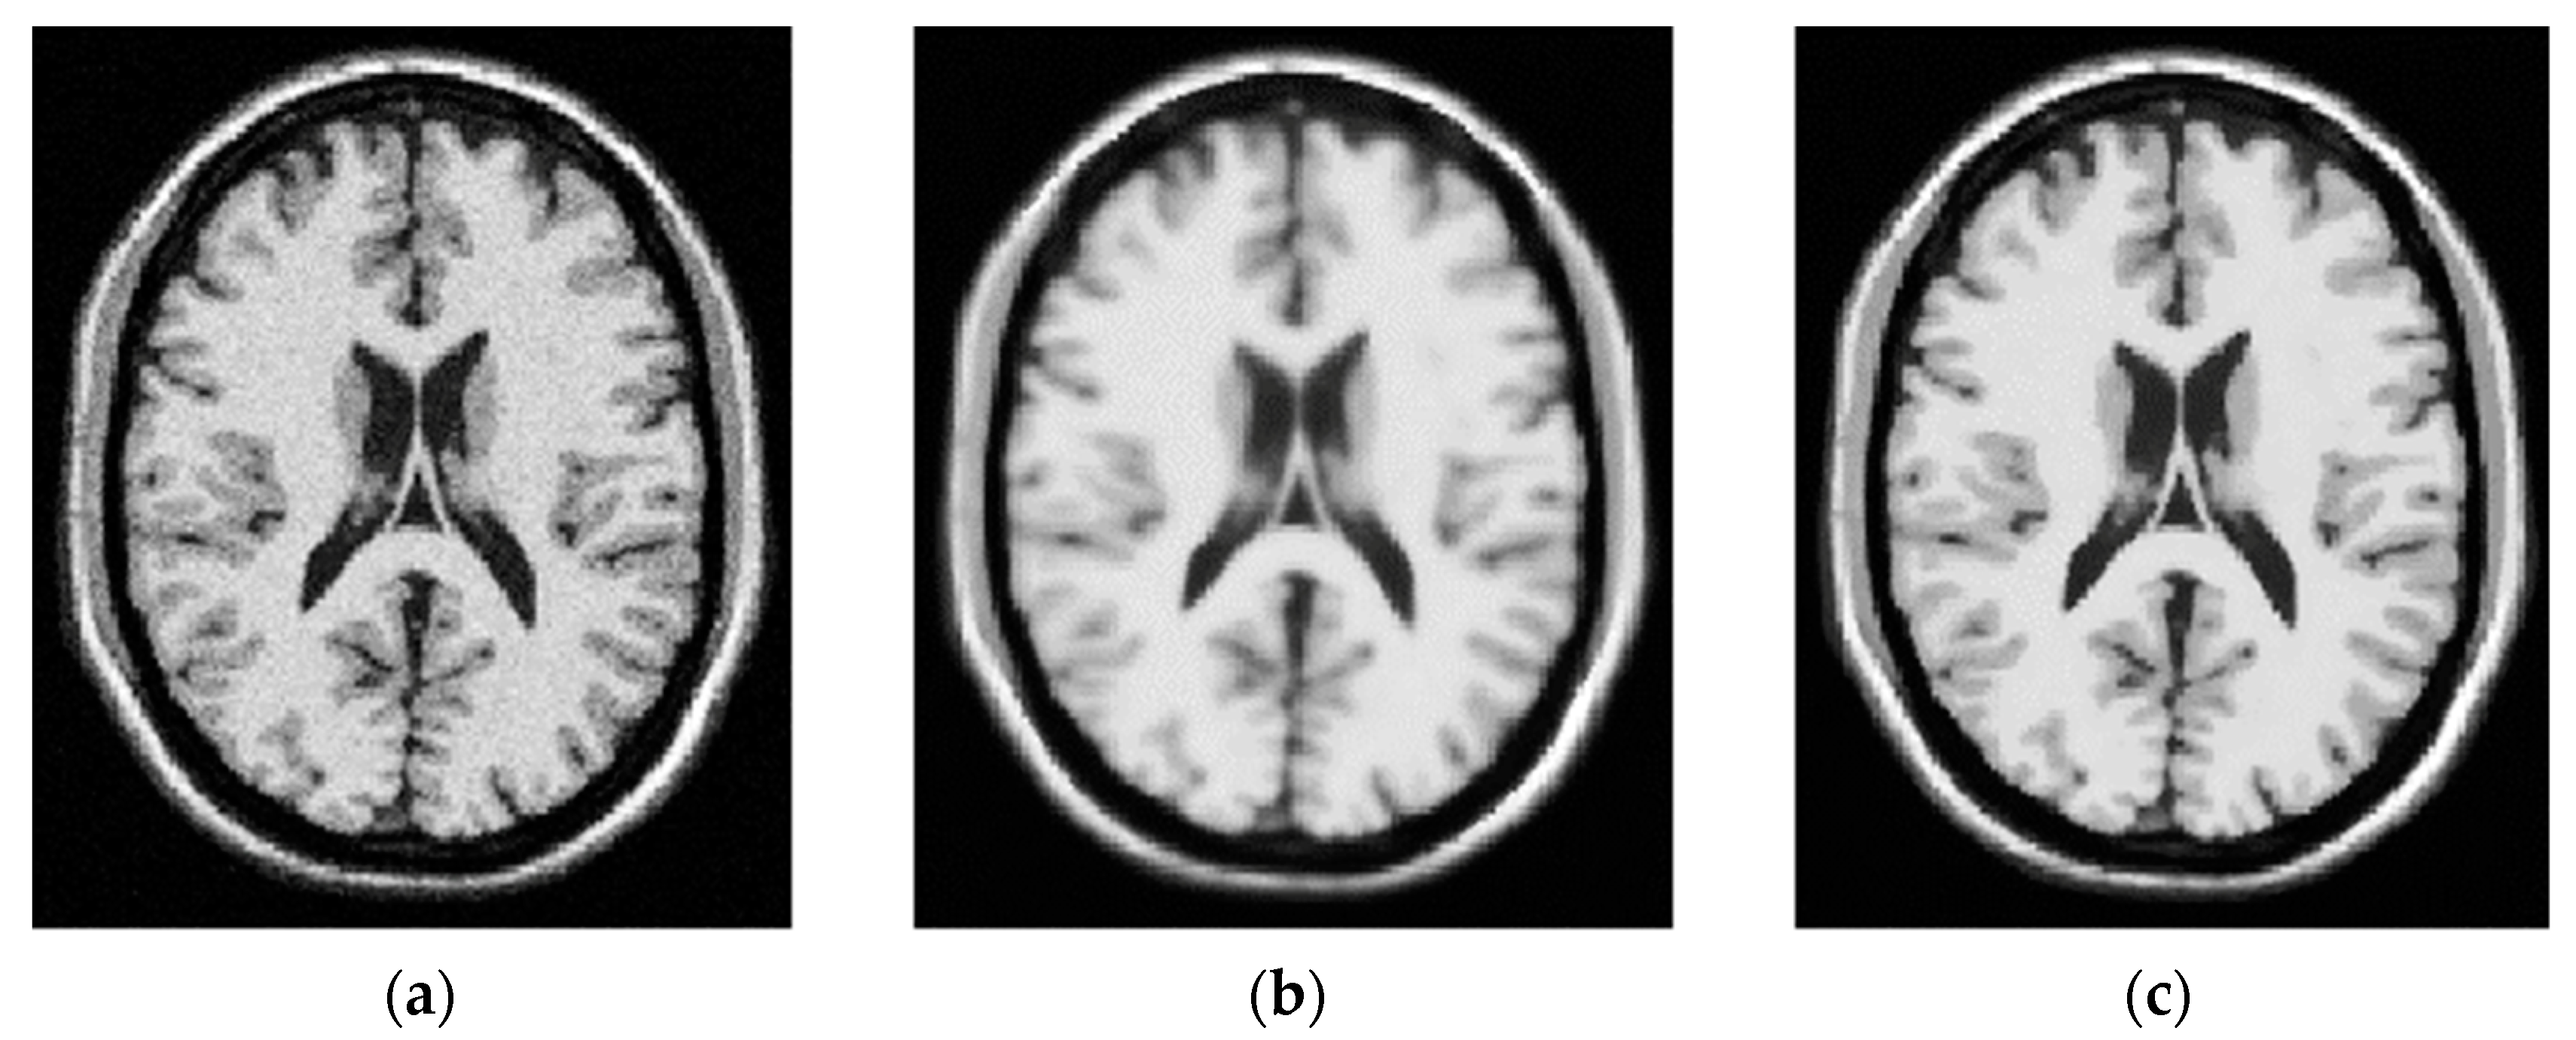

- Jin, R.; Tong, D.; Chen, Z. Level-set-based multiplicative intrinsic component optimization for brain tissue segmentation in T1-W and T2-W modality MRI. Expert Syst. Appl. 2023, 224, 119967. [Google Scholar] [CrossRef]